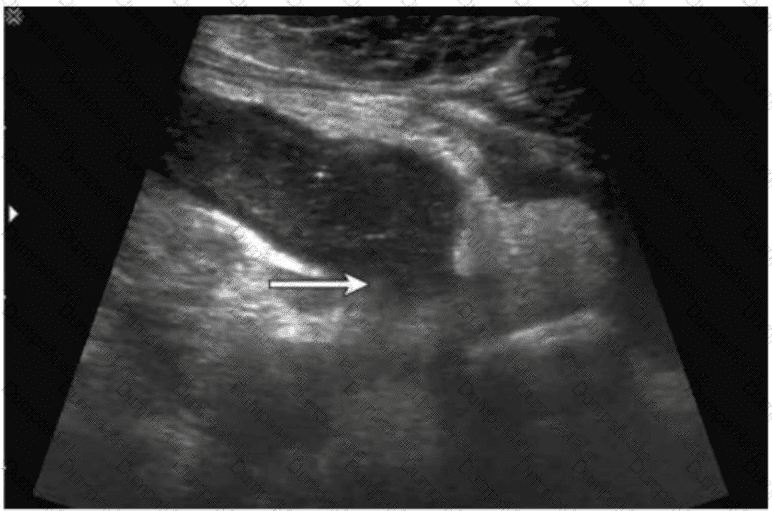

Questions 28

Which condition is most consistent with the findings in this image?

AB-Abdomen Question 28

Options:

A.

Fungal balls

B.

Renal cell carcinoma

C.

Acute pyelonephritis

D.

Medullary sponge kidney

Buy Now